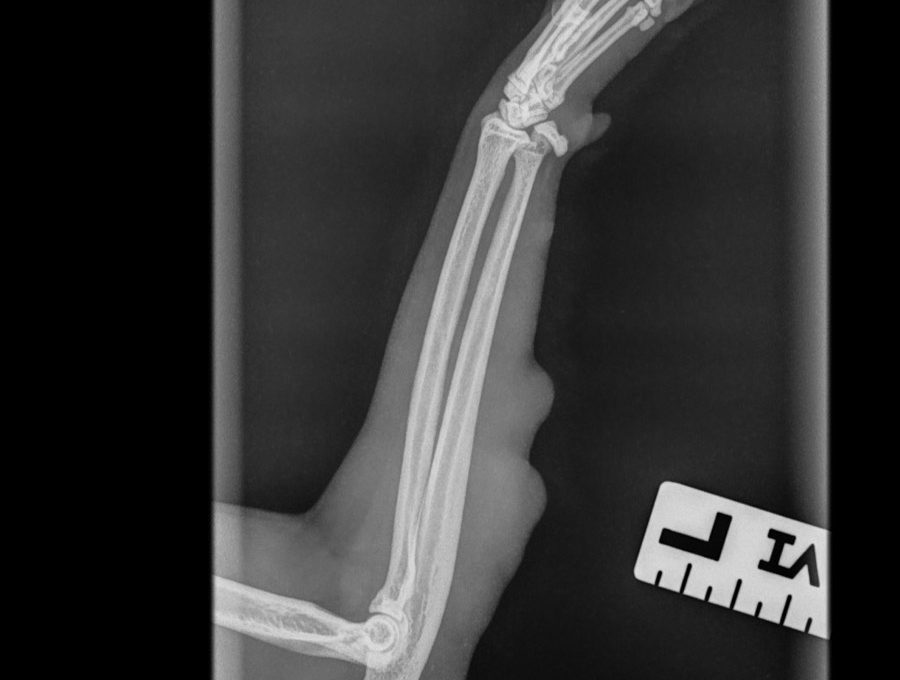

Niin, eli patti tosiaan tuli takaisin. Tänään käytiin Mörrin kanssa lääkärillä. Lääkärinä toimi Evidensia Nekalan Virpi Arminen, joka on ihan huipputyyppi ja varsinkin kirurgina todella loistava. Hän teki Mörrin ensimmäisenkin kasvaimen poisto-operaation ja PESUn eläinten kanssa ollaan käytetty hänen palveluitaan paljon. Kasvain on kasvanut etujalan lihakseen pituudelta kiinni. Jalasta otettiin röntgenkuvat, joissa selvisi että luihin … Read more